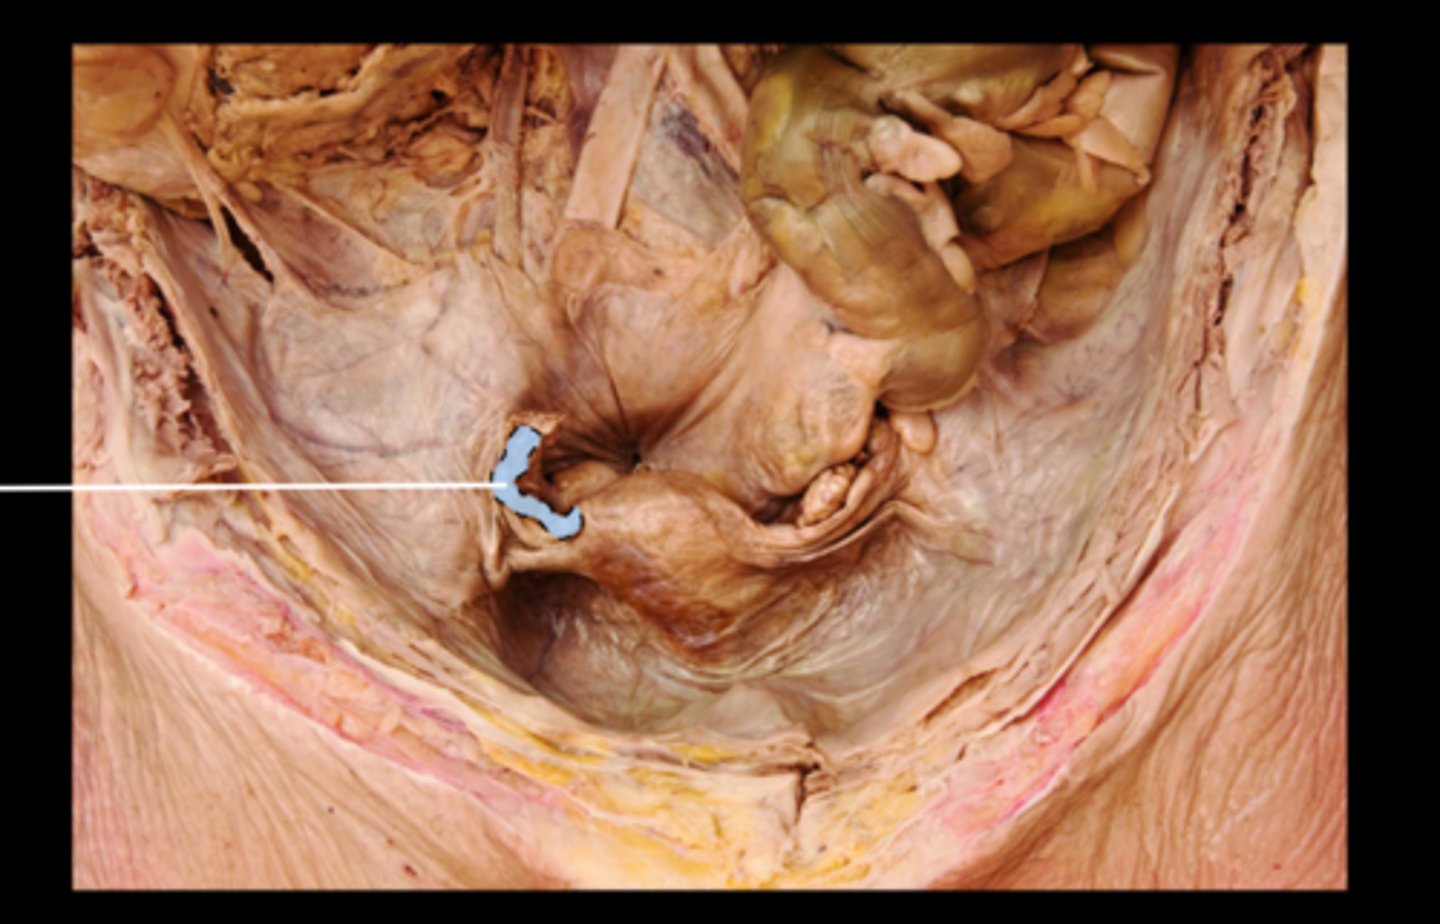

Anal Canal